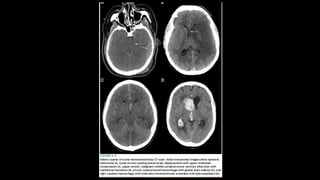

A) Causas Estruturais

1) Lesão direta no TE (AVC, dça desmielinizante):

2) Lesões focais, com grande efeito de massa HIC

Hérnias Compressão TE

3) Condições que comprometam encéfalo globalmente

(geralmente causas metabólicas)